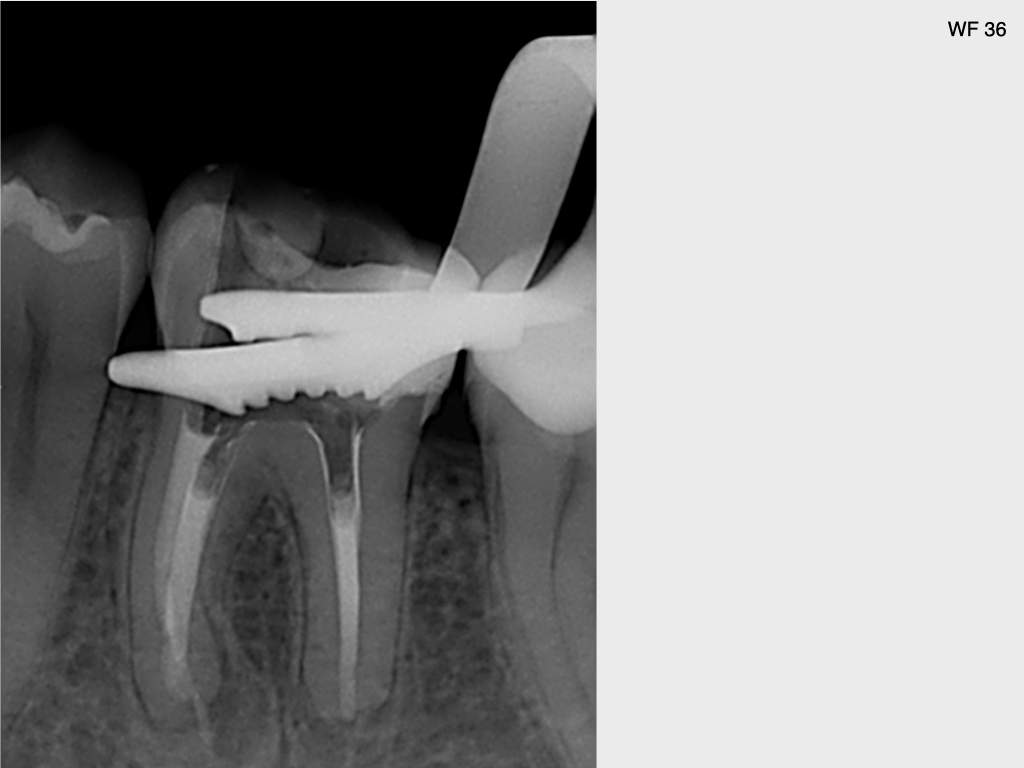

6624.007

25. Juni 2021

1024 × 768

10 Jahres Recall